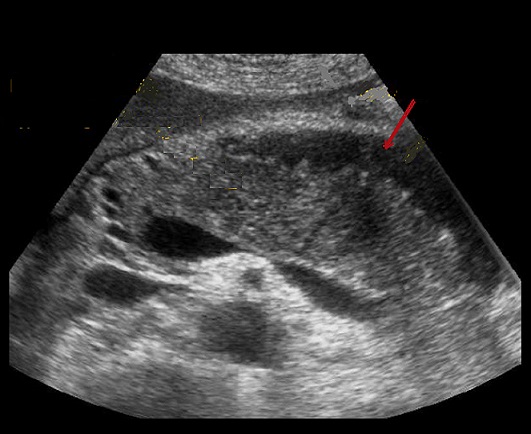

Image echographique d'un

pancreatite aigue au stade debut . Le pancreas est

volumineuse , diametre du corp > 2,4cm . Le

parenchyme est oedemateuse avec couche epanchement

discrete peripancreatique |